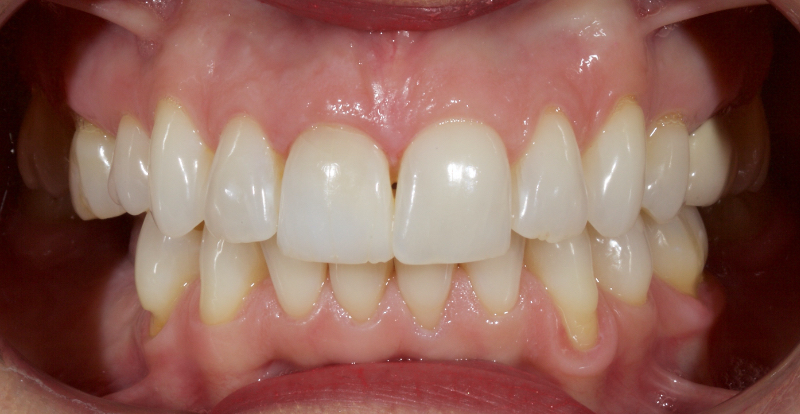

This article explores a more modern, minimally invasive approach to discolored non-vital teeth using the “modified walking bleach” approach. Figure 3 (before treatment) and Figure 4 (after treatment) show an example of this highly conservative approach.